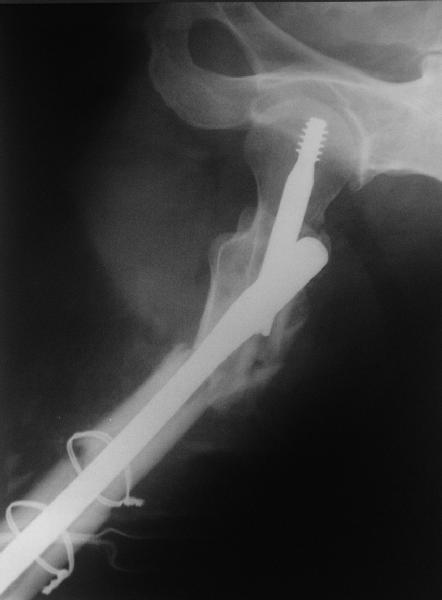

В общем, сделали. См. приложение.

Длина и из-за этого ось получились не совсем такие, как хотелось бы, все-таки срок после той операции уже 6 недель. Может быть, стоило провести дистракцию аппаратом неделю-другую. Заранее спасибо за комментарии и критику.